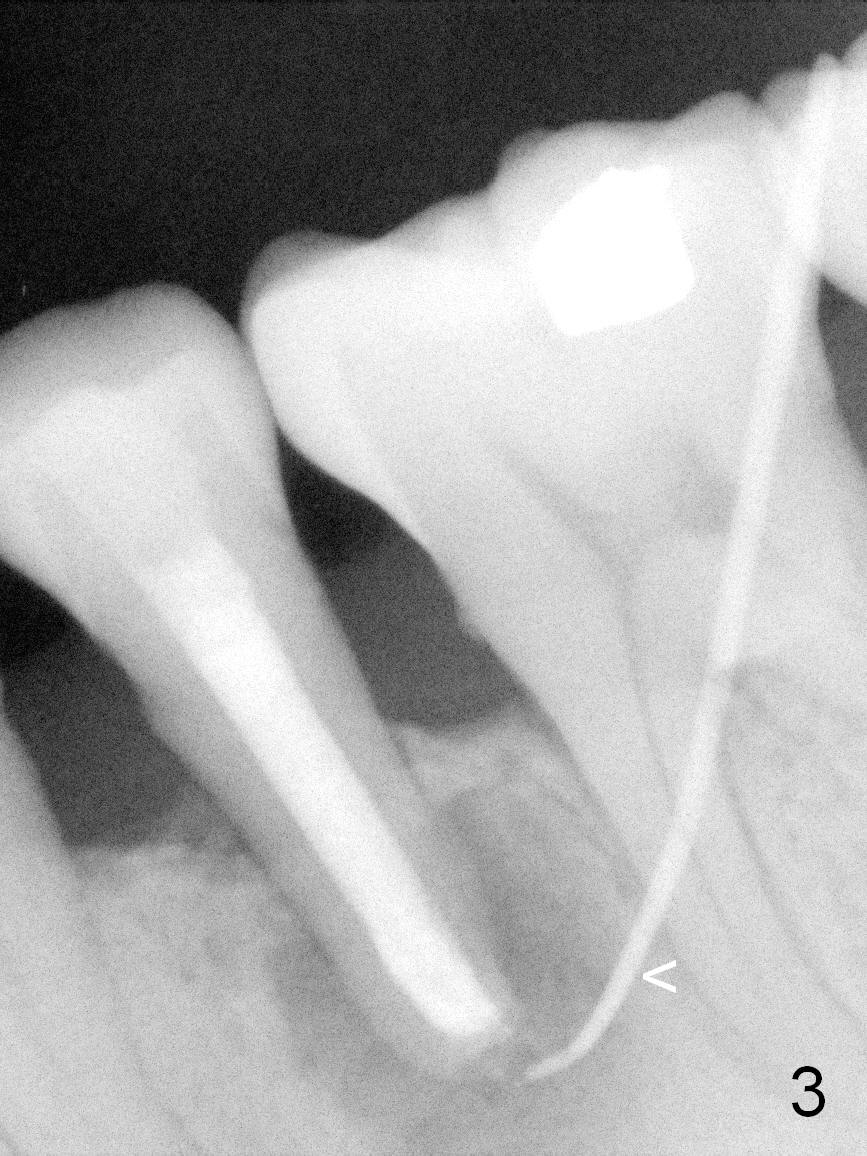

A 45-year-old man (JT) has endo failure at #20 with fenestration (Fig.1,2 black >) and fistula (white <). Insertion of a Gutta Percha at the fistula (Fig. 3 <; PA taken 2 years ago) indicates that the infection is dervied from the apex of the tooth #20. The socket will be soaked with 2% Xylo, 1:50,000 Epinephrine gauze. A 4.5x17 mm tissue-level (Fig.4) or 14 mm bone-level implant is placed as lingual as possible (Fig.5 green). If primary stability is achieved, an abutment is placed (pink). A large piece of resorbable membrane is used to cover the buccal defect (including buccal recession, fenestration and fistula (Fig.6 yellow dashed line). Two small pieces of non-resorbable membrane are placed to cover the gingival recession and the fenestration (Fig.7 white dashed line, buried underneath the edge of the gigniva). Then place bone graft buccally. Place a small piece of gauze (one layer) or plastic (from Tatum implant bag) over the 2nd membrane over the gingival recession and fabricate an immediate provisional. When the acrylic is partially set, remove the gauze or plastic from the provisional. After trimming and polishing, the provisional is cemented to securely keep the 2nd membrane in place. When the wound is healing and the 2nd membrane is stable, trim the buccal extension of the provisional. It is expected that the buccal hard and soft tissue will regenerate over the implant.